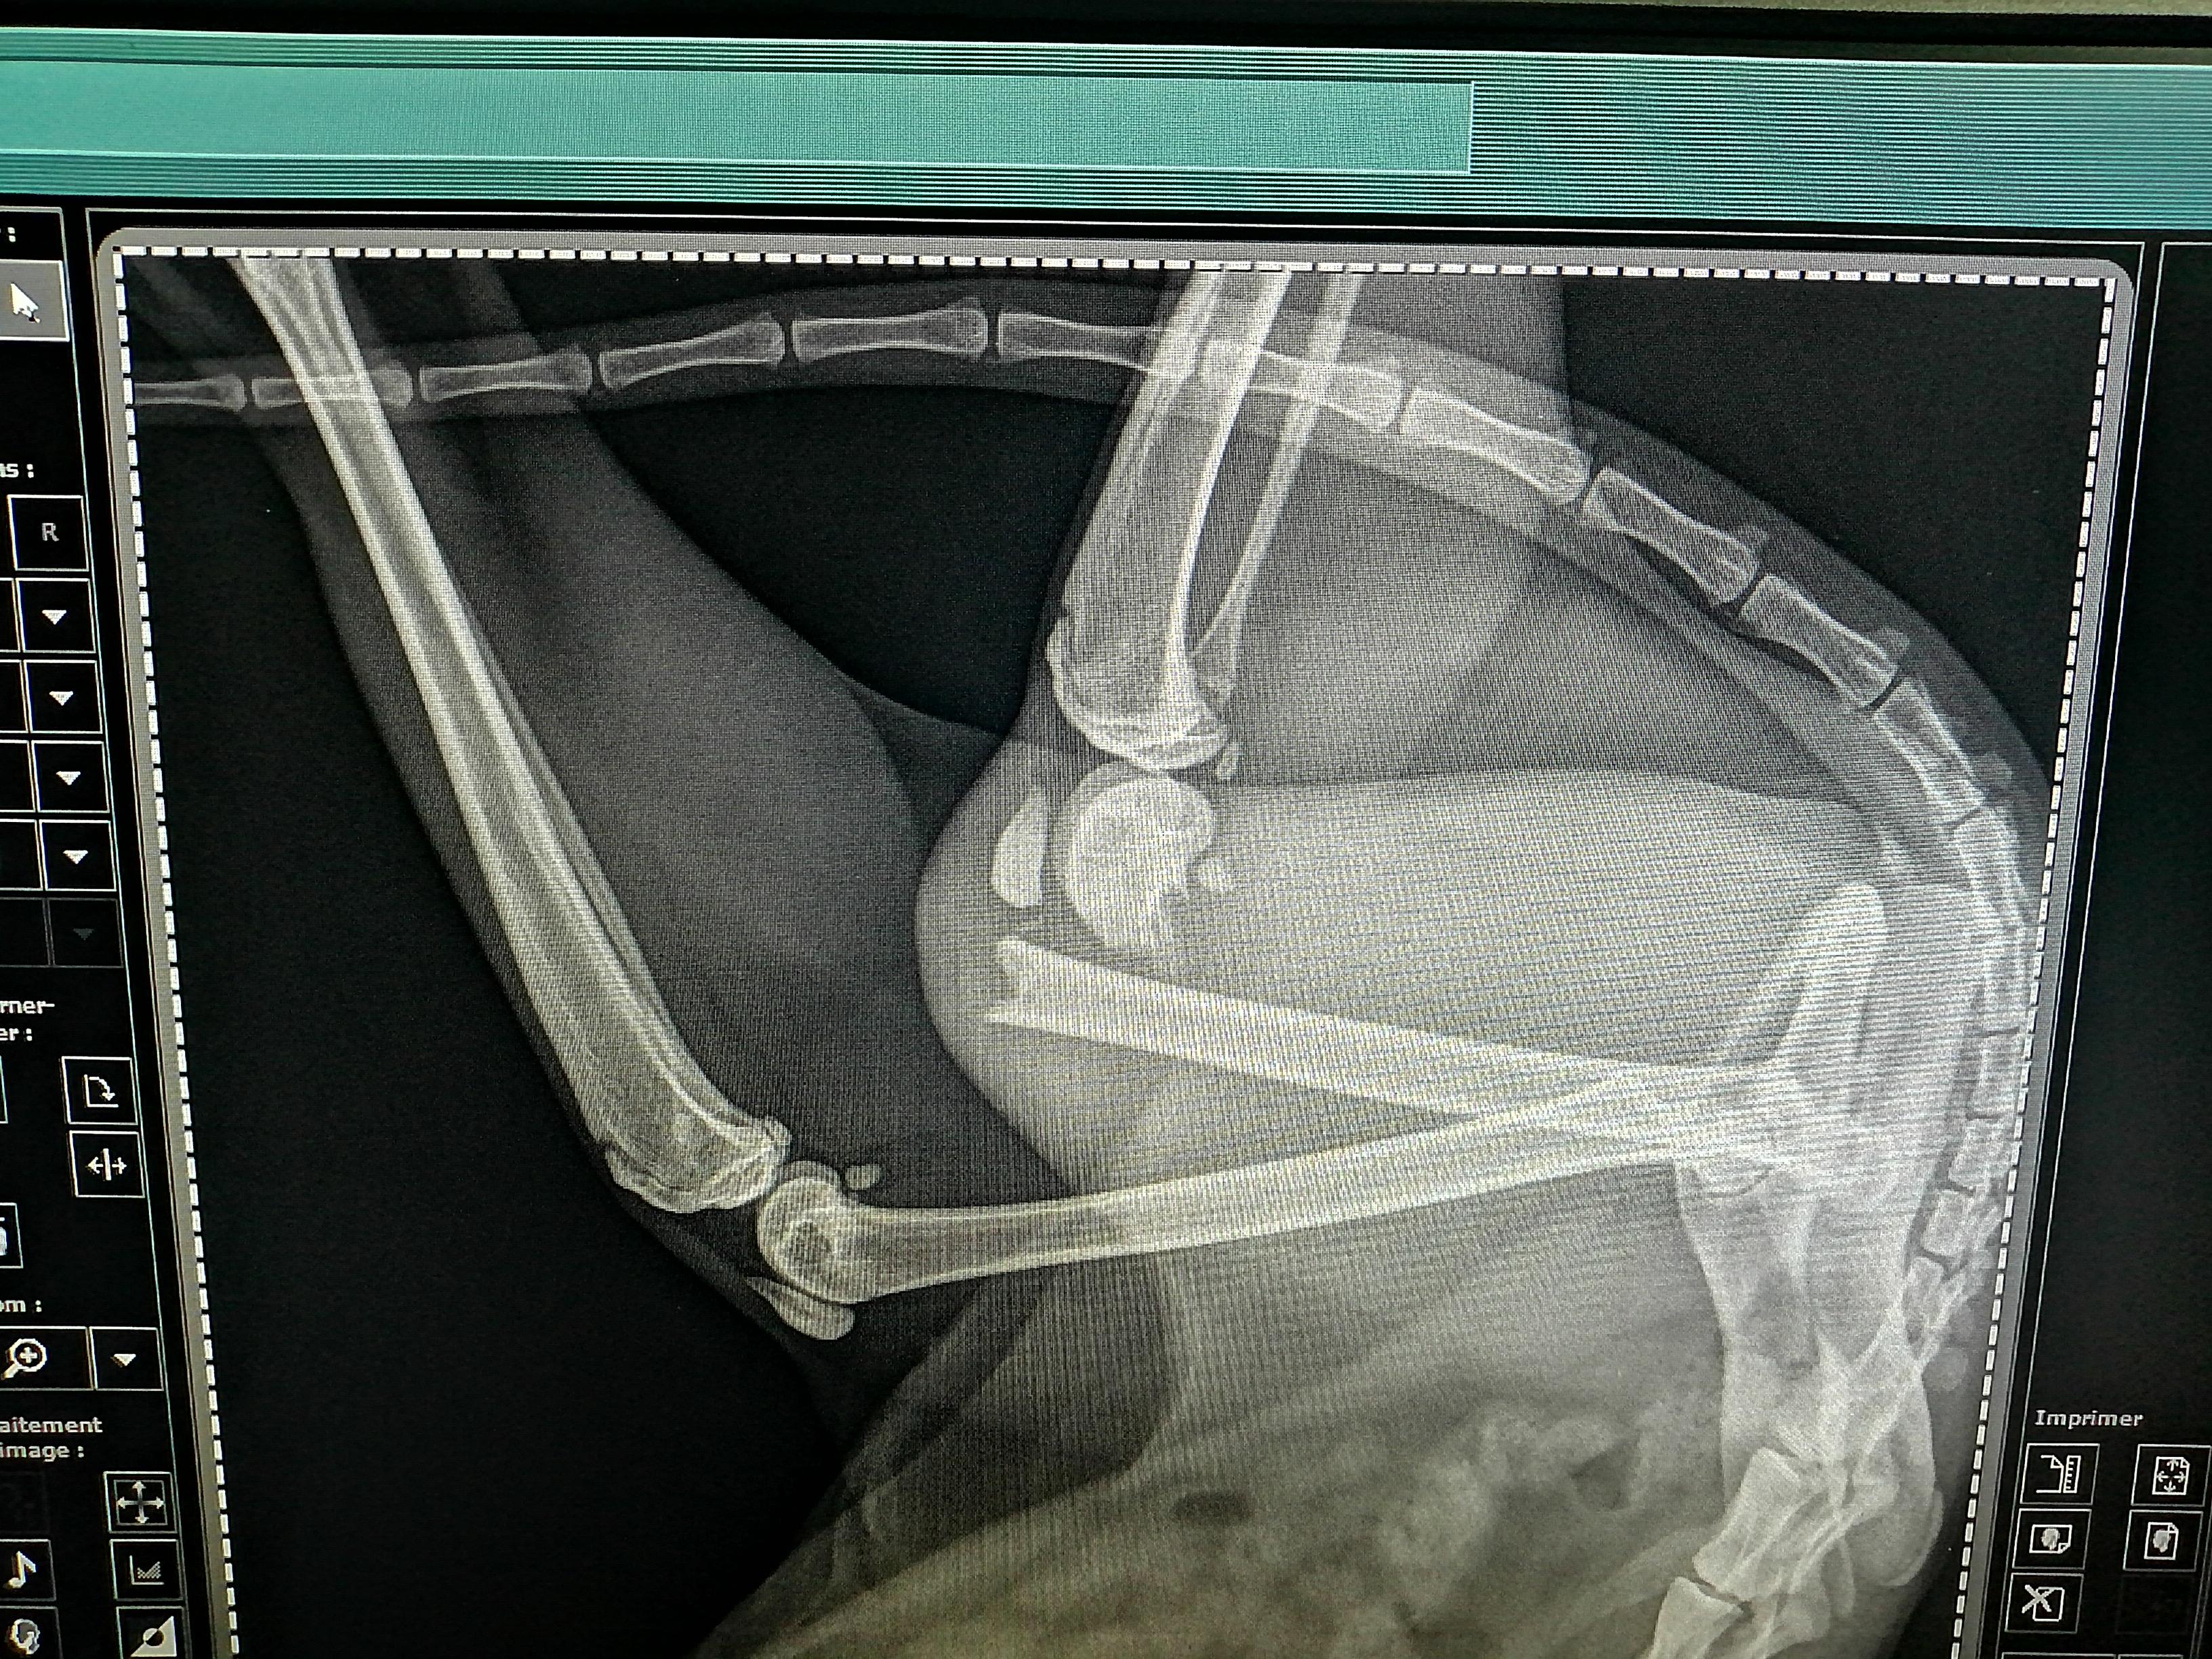

My 1-year-old cat has a broken leg. What are her treatment options?

What is your advice for this 1 yo female with broken leg. Operate or not, if yes what type of operation and what should be done

Yes, surgery is required, the bones cannot heal as the leg is unstable and the ends are not touching. The bones could be manipulated back into place and secured with pins or amputation could be considered